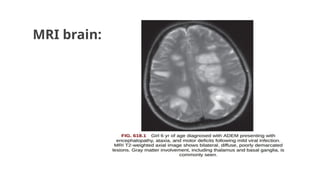

MRI (Imaging study of choice) • B/L large multifocal sometimes confluent edematous

mass like lesions with variable enhancement within

white & gray matter.

• Typically appears to be of similar age.

• Repeat MRI after 3- 12 months – improvement or

complete resolution.

MRI brain: